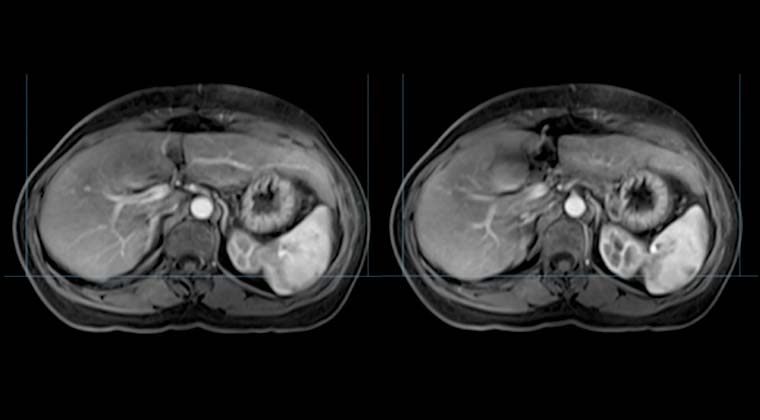

Контрольное МРТ 102021:

Изменения после комплексного лечения рака печени; очаги значительно уменьшились по сравнению с предыдущим обследованием.

Аденомиоматоз желчного пузыря, в целом без изменений.

После лечения: